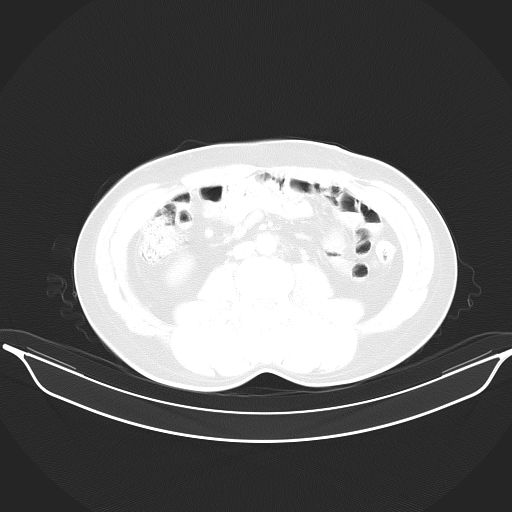

标题: CT25490:男,40岁,体检发现;无其它不适。 [打印本页]

标题: CT25490:男,40岁,体检发现;无其它不适。

2、轻度脂肪肝。

考虑右下肺周围性肺癌并肺内多发转移,纵隔淋巴结转移!

支持 !考虑右下肺周围性肺癌并肺内多发转移,纵隔淋巴结转移,(气管前腔静脉后,隆突下,主动脉弓下都有了)

1、均为转移,原发灶不在肺内。2、肺癌肺转移。